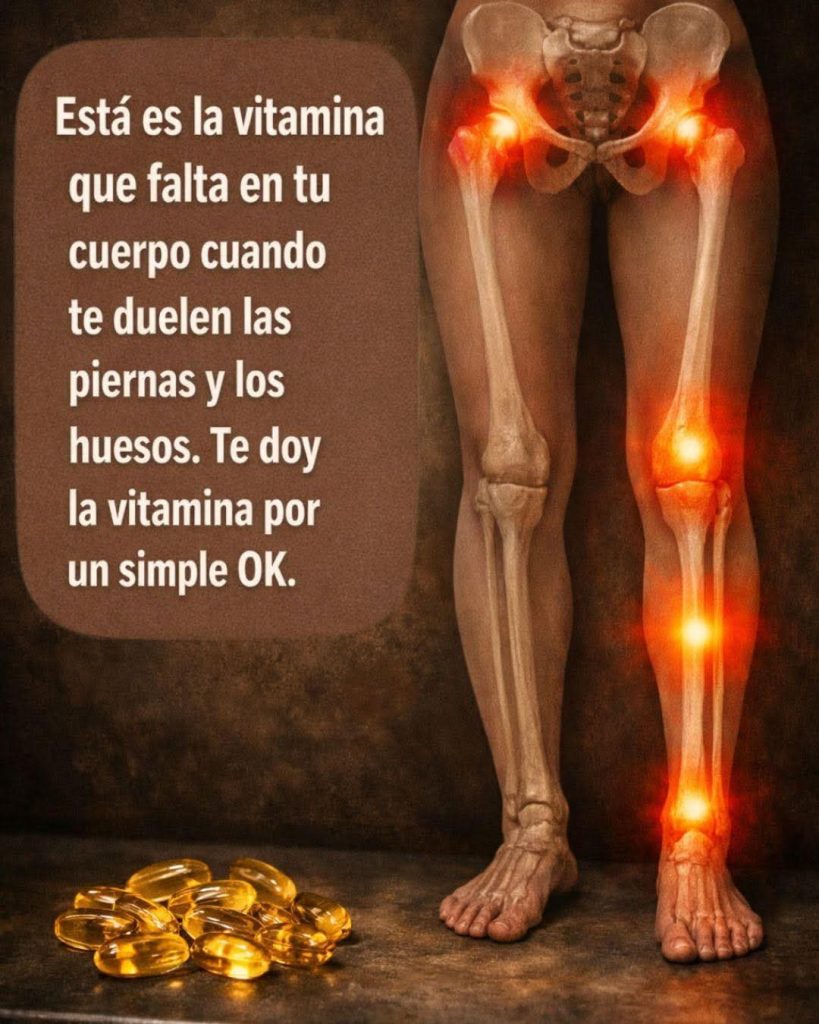

En redes sociales se ha popularizado la idea de que esto siempre se debe a la falta de una vitamina específica.

🚨 El mito viral

Algunas publicaciones aseguran que “solo necesitas una vitamina” para eliminar el dolor.

Esto es una simplificación excesiva.